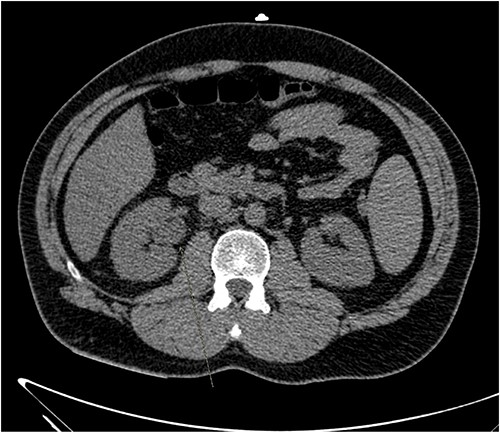

The patient was treated with IV piperacillin-tazobactam. However, he continued to have febrile temperature spikes. No growth was initially detected on blood cultures. The patient developed shortness of breath and respiratory alkalosis, for which a CT pulmonary angiography was done to exclude pulmonary embolism. Only dependent bilateral changes in the lower lobes and signs of mild pulmonary venous congestion were reported (Fig. 3). He was started on hydrocortisone, ethambutol, pyridoxine and rifampicin as empirical treatment for BCGosis. Hydrocortisone was eventually tailored down to prednisolone. Virology tests including hepatitis and immunodeficiency virus were run and these were negative. He continued spiking high temperatures and a repeat CT abdomen with IV contrast was performed which was largely unchanged from the previous scan (Fig. 4). An echocardiogram ruled out infective endocarditis. Incidentally he was in contact with a COVID-19 positive patient and was placed under quarantine for 14 days. Fortunately, he never developed COVID-19 infection. Another CT pulmonary angiography was performed in view of persisting shortness of breath but only mosaic attenuation in the lungs was present.

A CT pulmonary angiography was done to exclude pulmonary embolism. Only dependent bilateral changes in the lower lobes and signs of mild pulmonary venous congestion were noted.